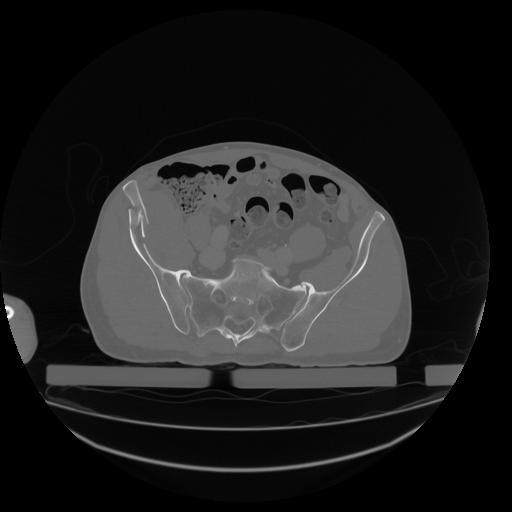

34 CUERPO,CE,Vol,1.0,CUERPO,,